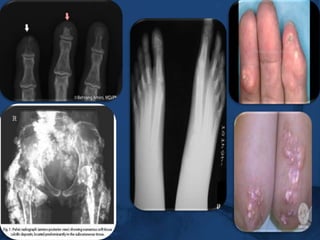

Resorption of terminal phalanges – acroosteolysis.

Diagnostic criteriaThe AMERICAN COLLEGE OF RHEUMATOLOGY (ACR) criteria for the classification of systemic sclerosis.One major criteria,two or more minor criteria for diagnosis.MAJOR criterion : PROXIMAL scleroderma –characterized by SYMMETRICAL thickening,tightening and induration  of the skin of the fingers and the skin proximal to the MCP /MTP joints. these changes may affect  the entire extremity,face,neck,trunk.MINOR1.SCLERODACTYLY – thickening,induration,tightening of the skin limited only to fingers.2.DIGITAL PITTING SCARS/LOSS OF SUBSTANCE FROM THE FINGER PAD–due to ischemia.3.BIBASILAR PULMONARY FIBROSIS-b/l reticular pattern of linear or lineonodular densities in basilar portions of the lung on CXR.diffuse mottling/honey comb lung  not attributable to primary pulmonary disease

SKIN featuresClinically evident skin thickening is the HALLMARK of SSc—distinguishes it from others..

ATROPHY of skin – slow healing ulceration on                                extensor surface of PIP joints.,volar pads.

DIGTIAL pits – healed ischemic ulcers.